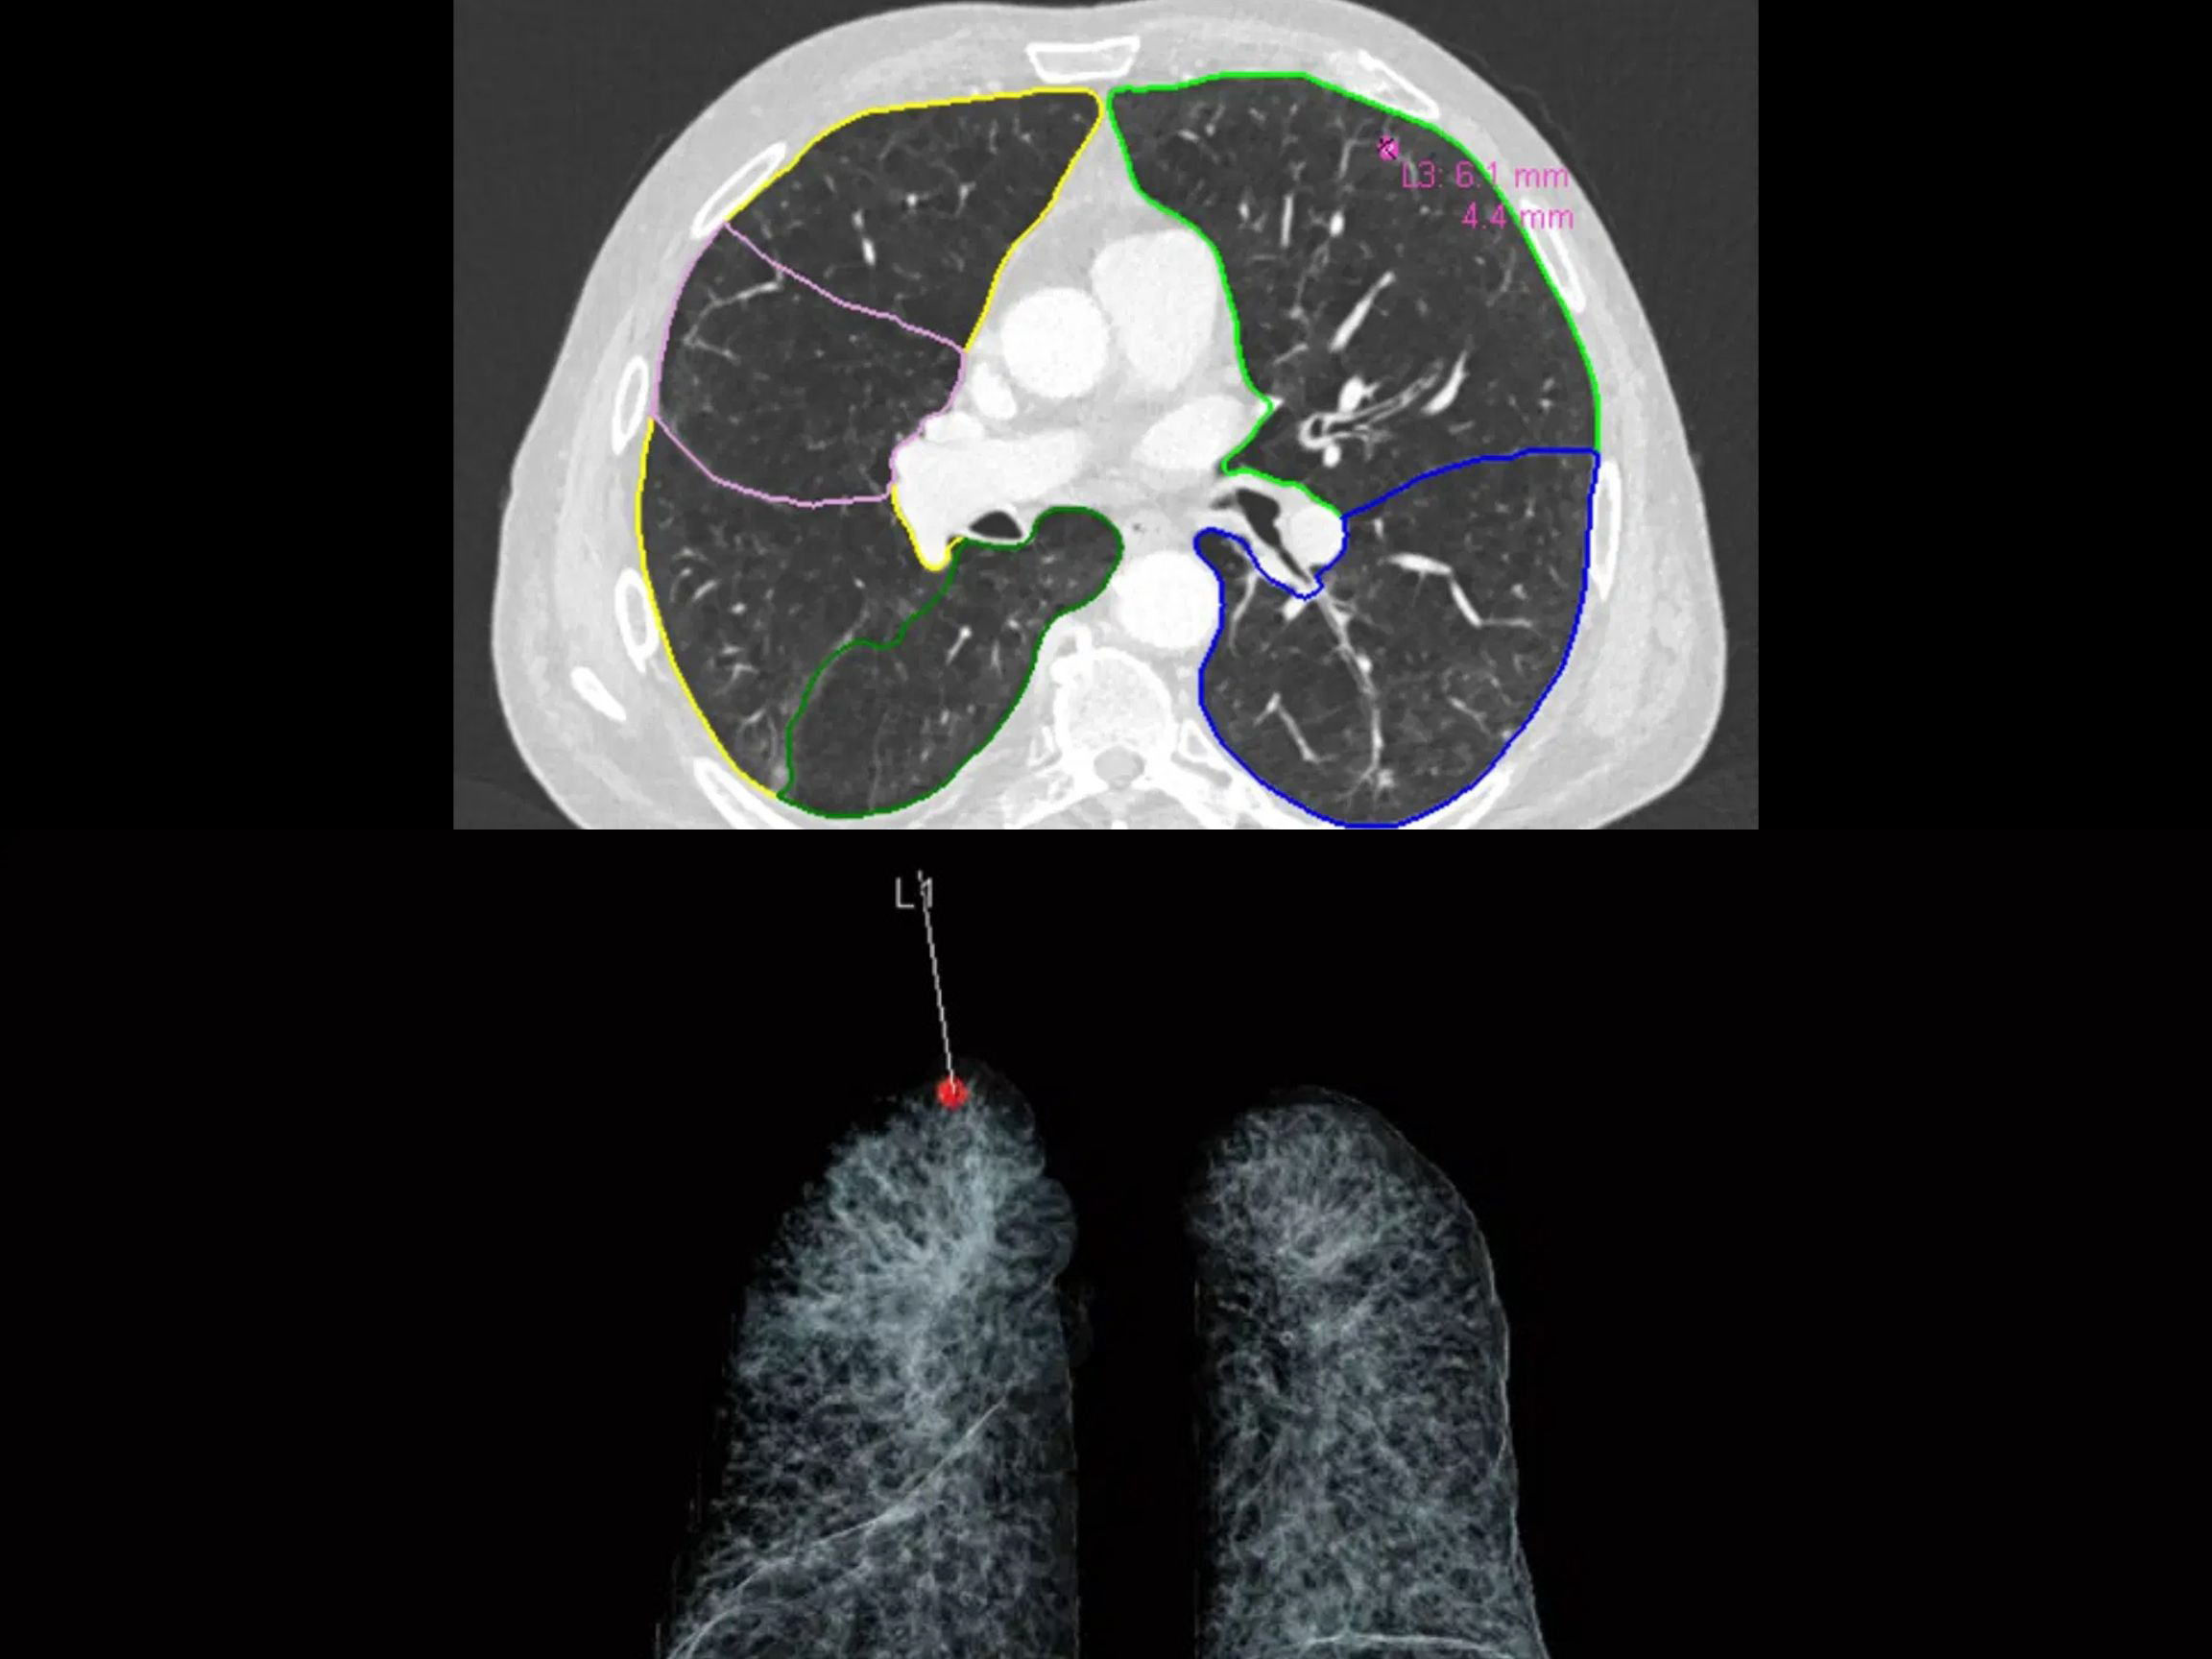

AI-Rad Companion es un conjunto de algoritmos de inteligencia artificial que ayuda a los médicos a acelerar el diagnóstico y la planificación terapéutica. A partir de un escaneo por tomografía (CT) o resonancia magnética (MRI), el sistema segmenta instantáneamente las estructuras anatómicas y distingue las células cancerosas para que sean objetivo de radiación, preservando los tejidos sanos.

Mediante el uso de OpenVINO™, el toolkit de código abierto de Intel para acelerar inferencias de IA, AI-Rad Companion puede identificar órganos y datos anatómicos. Esto le permite reconocer incluso las anomalías más pequeñas y alertar al médico sobre su ubicación y naturaleza.

Este sistema puede asistir en diagnósticos de enfermedades en pulmones, cerebro, próstata y trastornos neurodegenerativos como el Alzheimer. Al acelerar la planificación del tratamiento, contribuye a reducir los costos médicos.

AI-Rad Companion ayuda a los médicos a identificar, medir, caracterizar y cuantificar anomalías, lo que reduce el tiempo de interpretación en casos complejos de imágenes médicas. Y gracias a la flexibilidad de los procesadores Xeon Scalable, los centros médicos pueden usar el software tanto en la nube como en servidores locales.